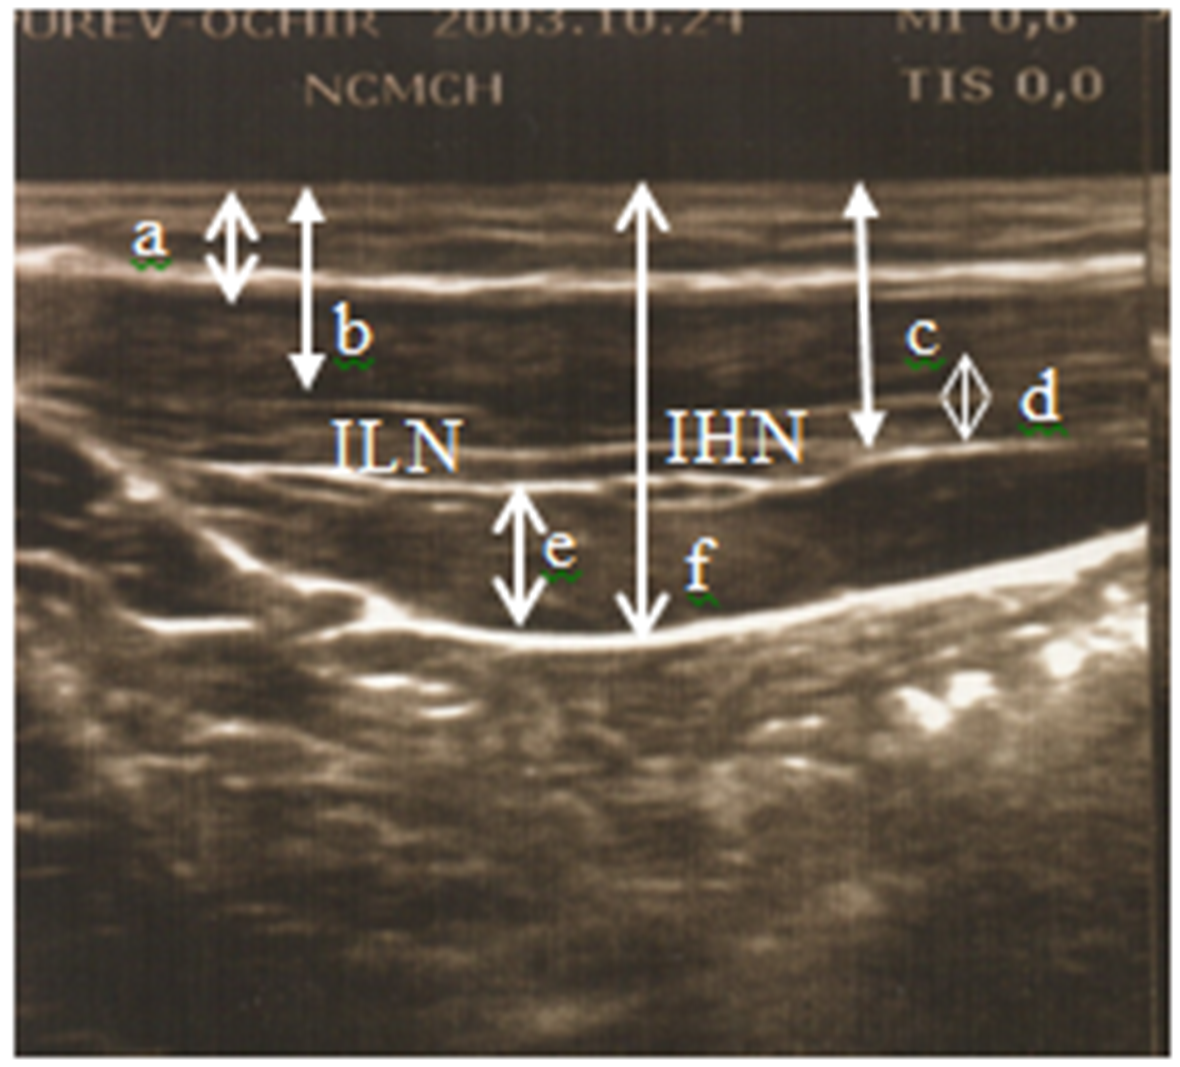

Ilioinguinal and Iliohypogastric Nerve Localization in Children: Our Initial Ultrasound Investigation

Odgerel Boldbaatar, Ganbold Lundeg, Sergelen Orgoi

International Journal of Innovative Research in Medical Science·February 26, 2022